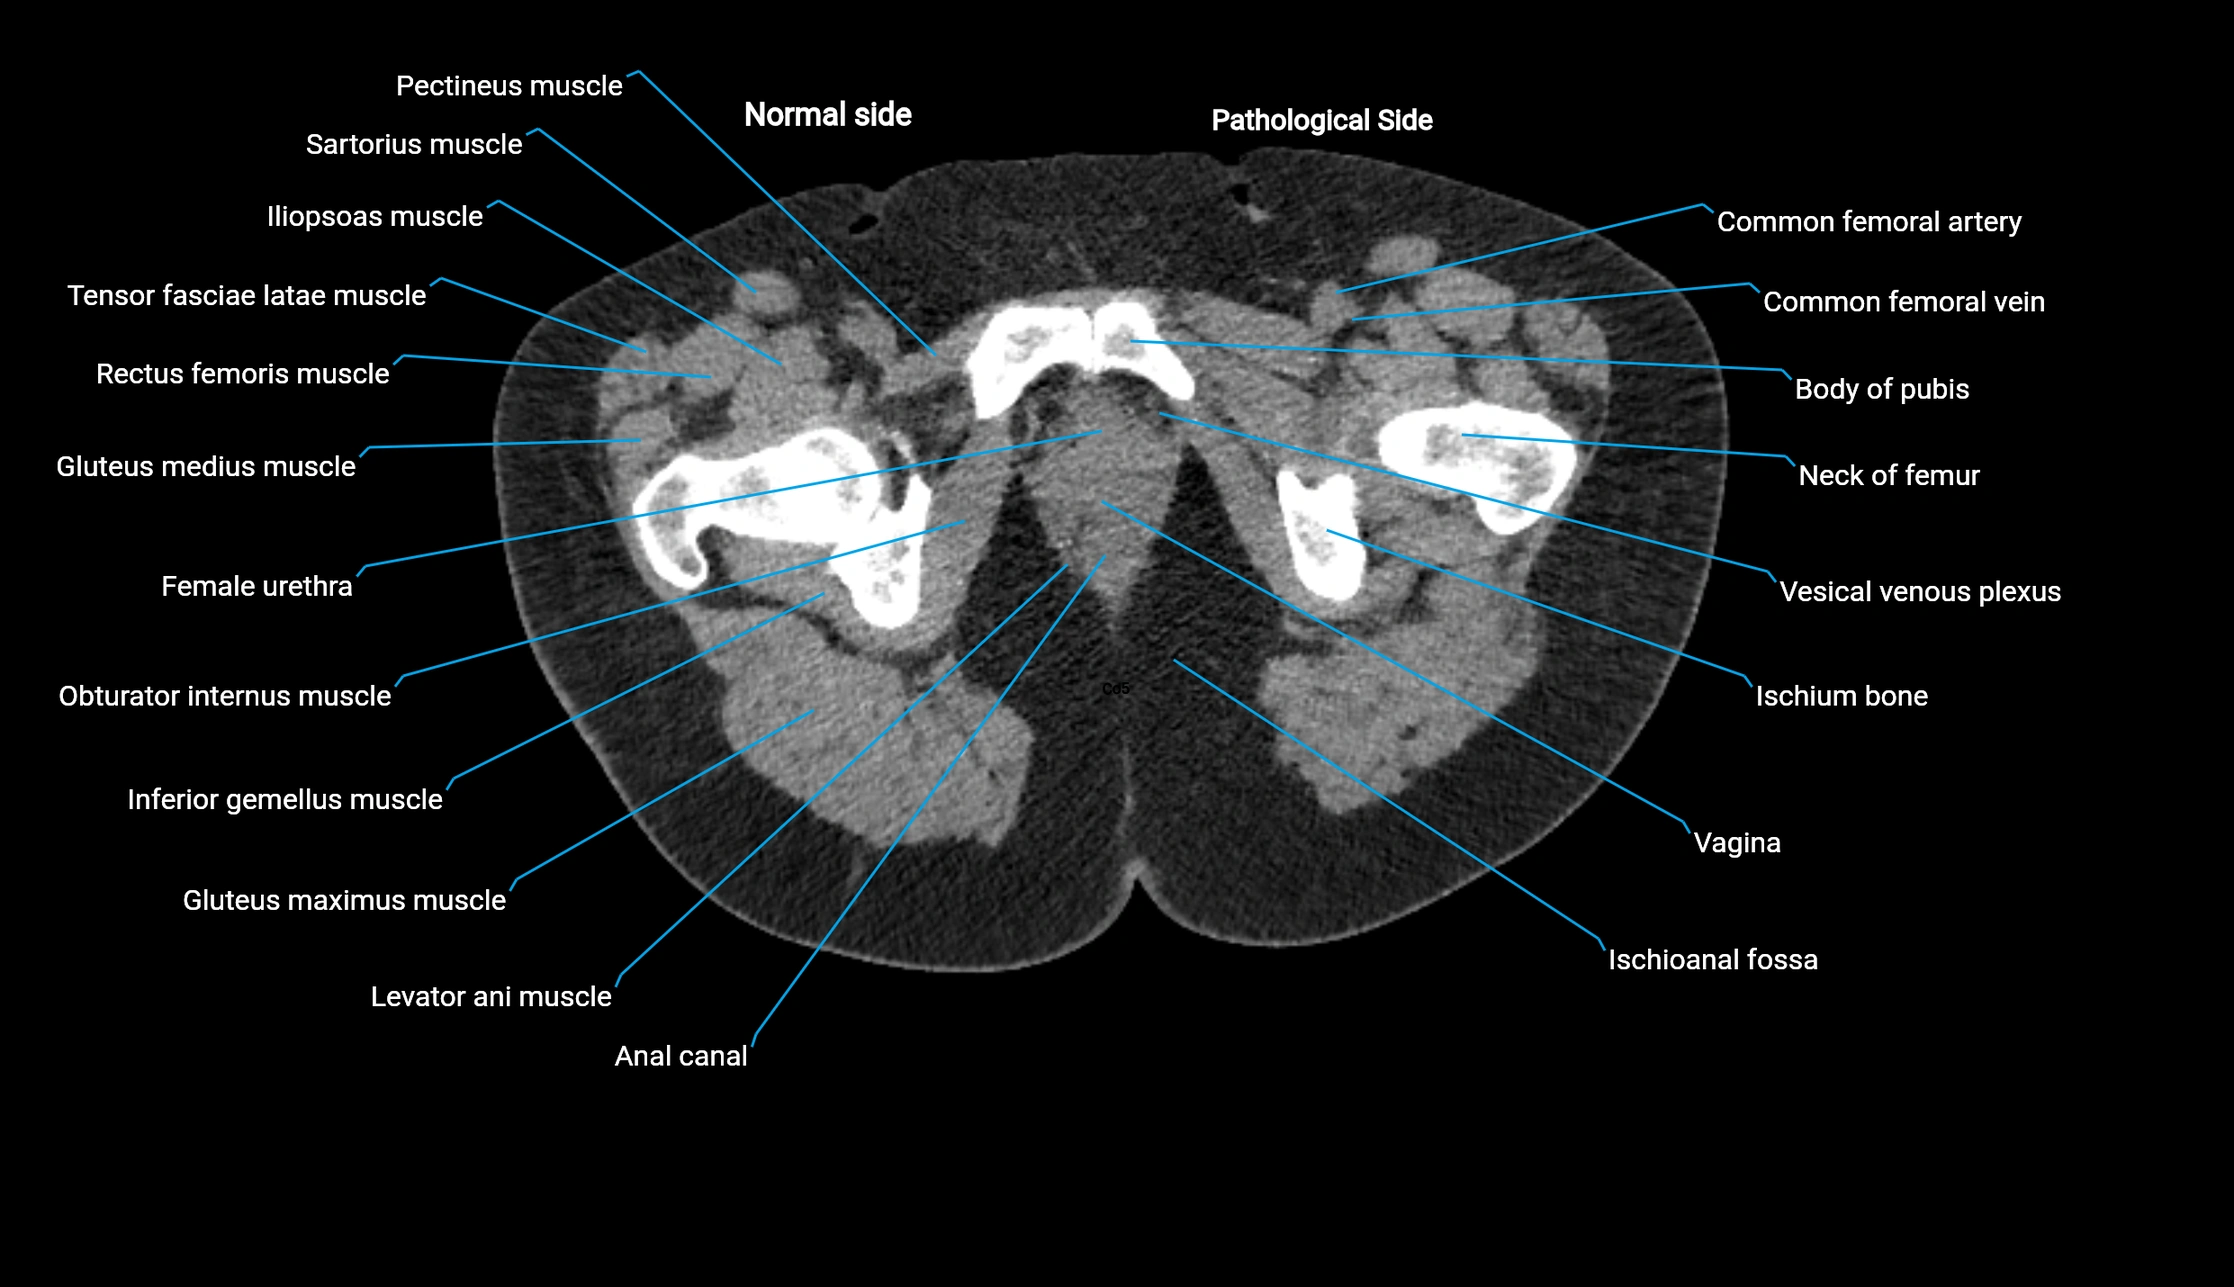

CT image

image